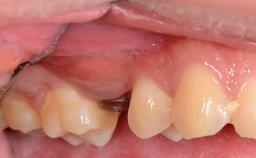

The patient presented with a failing tooth-supported fixed dental prosthesis with cantilever extension replacing the right maxillary central incisor. His chief presenting complaint was poor esthetics, in particular the dark discolored margin around the abutment tooth, the maxillary left central incisor. He reported a history of trauma at a young age, which necessitated the replacement of his maxillary right central incisor as well as root canal therapy of the adjacent left central incisor. The existing prosthesis had been in situ for over 20 years. The initial periapical radiograph displayed good proximal bone levels at the adjacent teeth and a wide incisive canal, which was a concern. The left central incisor presented a very wide root canal treatment with compromised radicular dentin thickness, which was a consideration in the decision between a new tooth-supported fixed dental prosthesis vs. an implant-supported prosthesis. After a lengthy discussion on the risks and benefits of both treatment options, the patient decided on a single-tooth implant replacement.

Soft Tissue Contour and Volume Slightly compromised